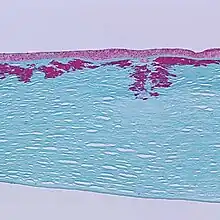

| Reis-Bücklers corneal dystrophy. Reticular opacity in the superficial cornea | |

Patients with Reis-Bücklers dystrophy develop a reticular pattern of cloudiness in the cornea. This cloudiness, or opacity, usually appears in both eyes (bilaterally) in the upper cornea by 4 or 5 years of age. The opacity elevates the corneal epithelium, eventually leading to corneal erosions that prompt attacks of ocular hyperemia, pain, and photophobia. These recurrent painful corneal epithelial erosions often begin as early as 1 year of age.[1]

With time, the corneal changes progress into opacities in Bowman's layer, which gradually becomes more irregular and more dense.[1] Significant vision loss may occur.[2] However, vascularization of the cornea is not present.[2]